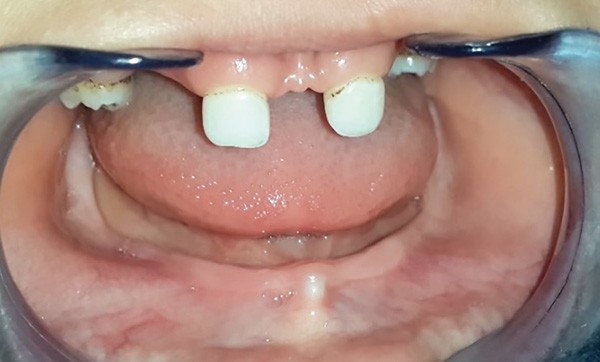

La dysplasie ectodermique hypohidrotique (DEH), ou syndrome de Christ-Siemens-Touraine, fait partie d’un groupe hétérogène de pathologies caractérisées par l’altération congénitale des structures dérivées de l’ectoderme. Elle se manifeste par une triade de signes : une hypohidrose/anhidrose, une hypotrichose et une hypodontie/anodontie. L’absence de dents constitue un handicap fonctionnel et esthétique pour les enfants atteints, qui doivent faire l’objet d’une prise en charge précoce et multidisciplinaire pour pallier les problèmes engendrés par ce syndrome. Une réhabilitation prothétique transitoire chez le jeune enfant est ainsi importante pour son développement psychoaffectif et son intégration scolaire. Cet article présente un cas clinique en exposant les différentes étapes de la prise en charge prothétique d’une petite fille atteinte de dysplasie ectodermique et présentant une hypodontie maxillaire et une anodontie mandibulaire.

Ce sont les raisons pour lesquelles le capital dentaire doit être préservé au maximum par des restaurations et des réhabilitations prothétiques précoces. Celles-ci doivent tenir compte de la croissance des enfants atteints afin de leur permettre d’arriver à l’âge adulte sans problèmes esthétiques, fonctionnels et parodontaux majeurs (fig. 1 à 9).